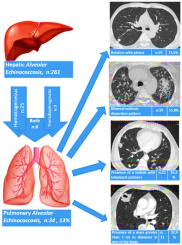

Các ấu trùng của loài sán dây Echinococcus spp., đặc biệt là loài E. granulosus, là tác nhân gây ra bệnh nang sán. Bệnh này đã được báo cáo xuất hiện ở Nam Mỹ, khu vực Địa Trung Hải, Trung Đông, châu Phi cận sa mạc Sahara, Nga và Trung Quốc và tỷ lệ lưu hành bệnh được ước tính lên đến 79 trường hợp trên 100.000 người. Bệnh nang sán phổi chiếm 20-30% trong số các ca bệnh nang sán.

Biểu hiện chính của bệnh được phát hiện ngẫu nhiên trên các hình ảnh chụp X-quang. Tuy nhiên, bệnh nhân có thể trải qua các triệu chứng như ho, ho ra máu, đau ngực hoặc tràn khí màng phổi. Các hình ảnh chụp X-quang của bệnh nang sán phổi khác nhau giữa E. granulosus và E. multilocularis. Bệnh nang sán do E. granulosus,khi các nang chưa bị vỡ, sẽ tạo ra các nốt hoặc khối có bờ mịn và không bị vôi hóa. Ngược lại, loài E. multilocularis gây ra bệnh Echinococcosis phế nang (Alveolar Echinococcosis) và trên hình ảnh chụp X-quang hoặc CT scan, bệnh này xuất hiện dưới dạng các nốt hoặc khối có hình dạng tạo thùy và có sự vôi hóa.

Hình 8. Tổn thương phổi do sán dây Echinococcusspp.  |